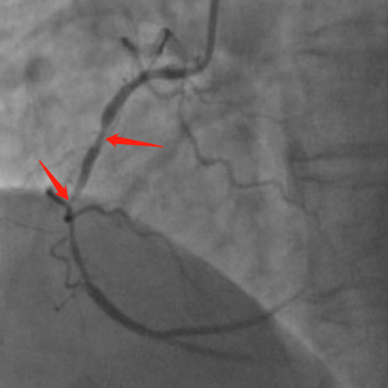

现场医生立刻电话联系心内科,必须尽快恢复患者冠脉灌注!门诊部进行快速核酸检测,但核酸结果出来至少需要几个小时,没有核酸结果,增加了疫情防控风险,但是在生命面前,及时救治更为重要!陈红主任和刘健副主任果断决定立即启动胸痛中心绿色救治通道,升级防护尽快为患者实施介入手术。冠脉造影证实了心电图的结果右冠状动脉近段和中段80%,99%狭窄。医护人员披上铅衣铠甲,穿戴上密不透风的防护服和防护面罩。术者、助手、护士、技师每个人都精神高度集中,分工明确,紧密协作。

16:00,宋俊贤和张静医生迅速完成导丝通过球囊扩张及支架置入,而此时距离患者发生胸痛仅有60分钟,达到了急性心肌梗死治疗指南中FMC-to-W(首次医疗接触到导丝通过)不超过60分钟的国际标准,时间就是生命,时间就是心肌,及早成功开通梗死的血管是救治急性心肌梗死患者关键所在。